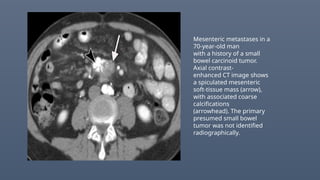

Mesenteric metastases in a

70-year-old man

with a history of a small

bowel carcinoid tumor.

Axial contrast-

enhanced CT image shows

a spiculated mesenteric

soft-tissue mass (arrow),

with associated coarse

calcifications

(arrowhead). The primary

presumed small bowel

tumor was not identified

radiographically.

Mesenteric metastases ina 70-year-old man with a history of a small bowel carcinoid tumor. Axial contrast- enhanced CT image shows a spiculated mesenteric soft-tissue mass (arrow), with associated coarse calcifications (arrowhead). The primary presumed small bowel tumor was not identified radiographically.